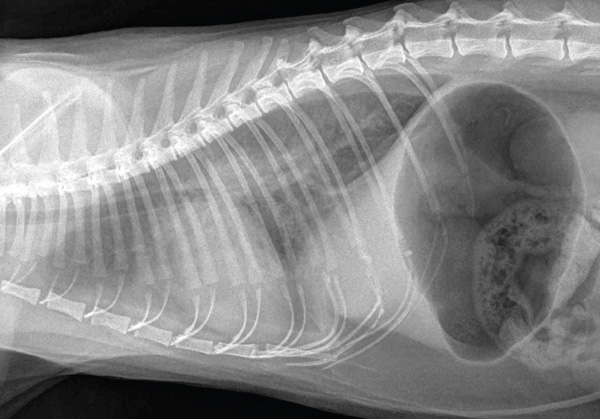

Further diagnostics should only occur when the patient is more stable. Radiography is crucial in assessing a patient with respiratory signs but should only be performed when the patients are more stable and it is possible to get a full three view chest series (dorsoventral, right and left lateral). All three views are required for a complete assessment of respiratory system. Conditions such as aspiration pneumonia may only be seen on a single lateral radiograph. It is important to remember that cardiomegaly is not always apparent on radiographs in cats and, therefore, it is necessary to rely on evidence of pulmonary venous congestion alongside an alveolar pattern to help make a diagnosis of congestive heart failure (Figure 8).

Figure 8. HCM and CHF